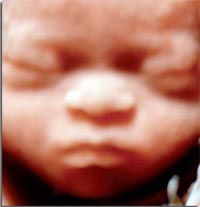

Paris, le mardi 7 février 2012 – Les discussions autour de la réforme des lois de bioéthique au printemps dernier ont ravivé le débat sur la mise en œuvre du dépistage prénatal de la trisomie 21. Quelques députés, soutenus par certains praticiens, réunis notamment au sein du « Comité pour sauver la médecine prénatale » défendaient en effet la nécessité d’atténuer le caractère systématique de ce dépistage. Ils souhaitaient qu’il ne soit proposé aux femmes enceintes que « lorsque les conditions médicales le nécessitent ». Cette suggestion et ce libellé ont finalement été fermement rejetés par les parlementaires, soutenus dans ce sens par une majorité de praticiens. Néanmoins, la polémique autour des possibles dérives eugéniques qu’entraînerait le dépistage actuel de la trisomie 21 et au-delà l’ensemble des diagnostics prénataux était relancée.

Les réflexions et positions des uns et des autres se sont de nouveau exprimées la semaine dernière à l’occasion d’un forum organisé à Strasbourg par le professeur Israël Nisand. Présents, les responsables du « Comité pour sauver la médecine prénatale » ont une nouvelle fois alerté sur les risques de dérives eugéniques. « On n’est pas dans la médecine de soins, mais dans la traque du handicap (…). L’enfant à venir est présumé coupable, il doit prouver sa normalité » a ainsi dénoncé le docteur Patrick Leblanc, gynécologue à Béziers. A ses yeux, le dépistage de la trisomie 21 tel qu’il est organisé aujourd’hui lui confère une dimension quasiment « obligatoire ».